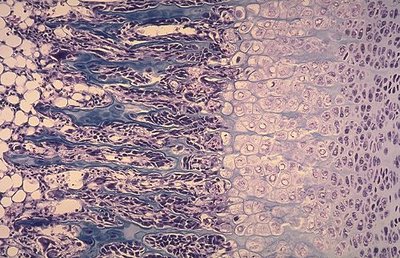

Alors en revoyant les cours du magnifique Ambrosetti à la douce voix de rondoudou, je me suis rendue compte que physiologiquement je savais sur une coupe la différence entre le cartilage hypertrophique et serié mais en soit, je ne sais pas en quoi ces deux cartilages diffèrent...